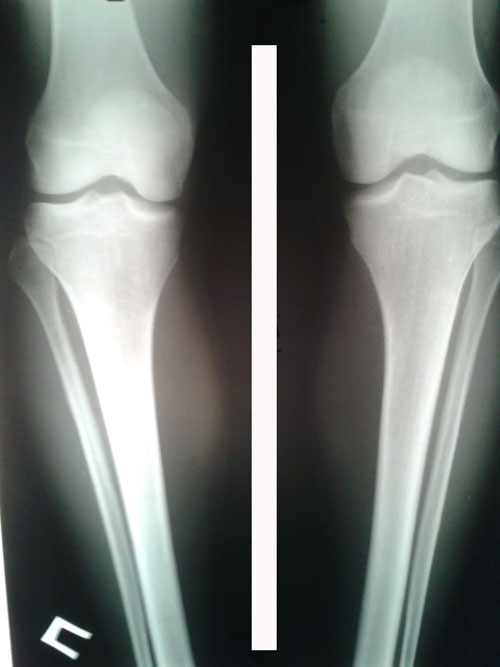

Исходник - 25 лет.

Дата операции 09.02.2016г.

Исходник отличный, внутренний контур голеней чётко выражен.

Рентген в 20 дней после операции.

Ортопедическая ось идеальная, искусство хирурга на 5+

Зафиксировать аппараты и домой!